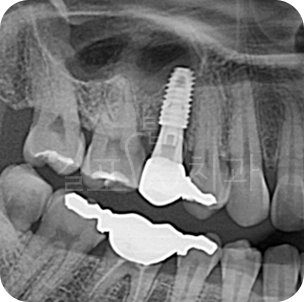

Before

After

• 치아 뽑은 자리 잇몸염증이 매우 심한 상태였습니다. 잇몸상태가 좋지 않아도

발치 즉시 임플란트를 시도할 수 있습니다. 다만, 2~3달 지난 후 수술한다면 더 안전하므로 이런 경우 즉시 식립을 추천드리지 않습니다. 발치 몇 달 후 상악동 거상술과 뼈이식 임플란트를 함께하여 수술을 완료하였습니다.